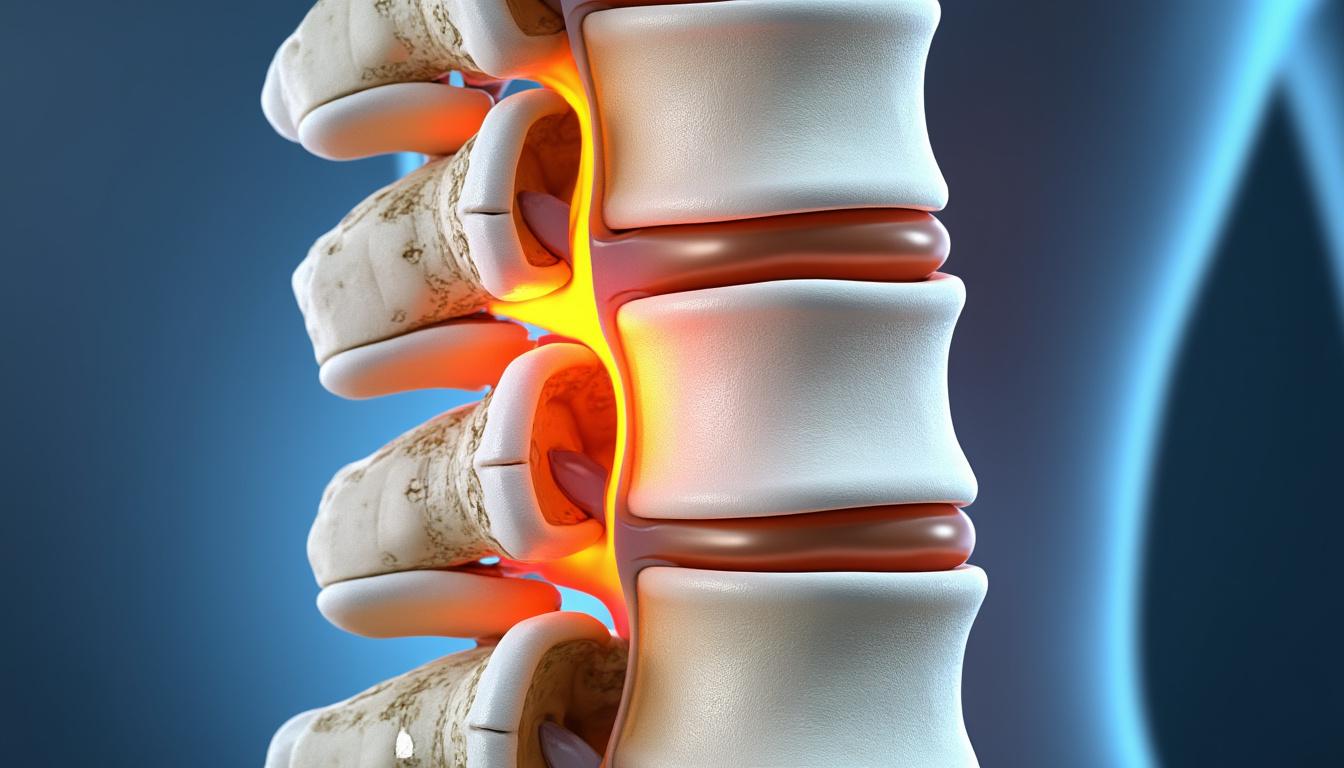

La hernie discale se manifeste par une protrusion ou une déchirure du disque intervertébral, ce qui provoque une compression des racines nerveuses ou de la moelle épinière. À Côte-des-Neiges–Notre-Dame-de-Grâce, où la densité urbaine est forte et la population active, nombre de patients souffrent de symptômes liés à cette pathologie. La douleur lombaire est souvent le premier signal, source de limitation importante dans la vie quotidienne.

Pour qu’un diagnostic précis soit posé, une évaluation clinico-radiologique est indispensable. L’imagerie médicale, notamment l’IRM, permet de visualiser la hernie et son impact sur les structures nerveuses. À la Clinique TAGMED, cette expertise est mise à profit pour différencier la hernie discale d’autres pathologies vertébrales comme les bombements ou les pincements discaux, garantissant un traitement adapté et ciblé.